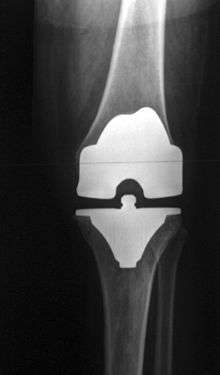

Femoral replacement

A round ended implant is used for the femur, mimicking the natural shape of the joint. On the tibia the component is flat, although it sometimes has a stem which goes down inside the bone for further stability. A flattened or slightly dished high density polyethylene surface is then inserted onto the tibial component so that the weight is transferred metal to plastic not metal to metal. During the operation any deformities must be corrected, and the ligaments balanced so that the knee has a good range of movement and is stable and aligned. In some cases the articular surface of the patella is also removed and replaced by a polyethylene button cemented to the posterior surface of the patella. In other cases, the patella is replaced unaltered.